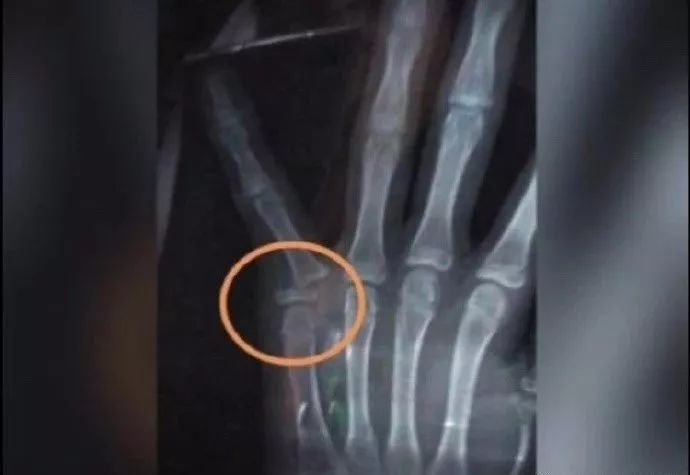

这位小哥哥是个狠人

自己把自己给掰骨折了

女人究竟有多狠,竟然可以连自己的手都可以不要

我是在乎我的手机吗?

是在乎我手机里面成千上万张的自拍~

看来“手”没有“手机”值钱,鉴定完毕~